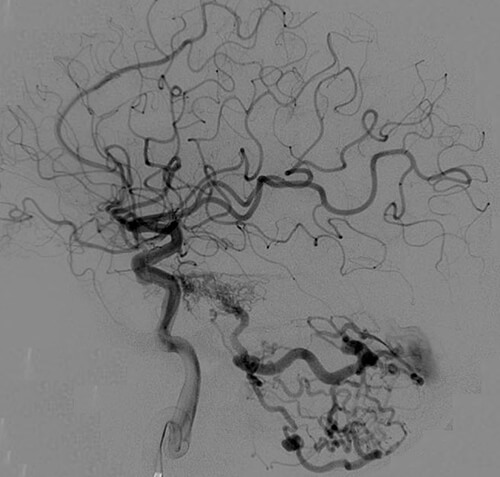

Η αξονική αγγειογραφία έχει ελαττωμένη ευαισθησία έναντι της μαγνητικής αγγειογραφίας.

Παρ´ όλα αυτά η συμβατική ενδαρτηριακή αγγειογραφία είναι η πιό ακριβής γιά την αναγνώριση αλλά και την κατηγοριοποίηση των ΑΦΔ της σκληράς μήνιγγας.